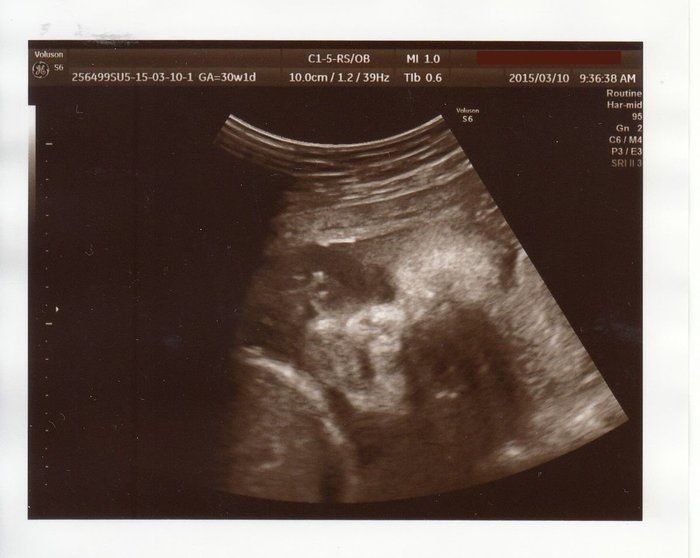

ママにエールさんの妊娠30週目のエコー写真

赤ちゃんは順調に成長して、推定体重1529g。気になっていた“逆子”の件は、無事に解決していました。妊婦検診までの期間ずっと、おなかの子に「頭を下にしてね~」と話していたのを、ちゃんと聞いてくれていたのかな…。などと思い、「お利口さん」とおなかをなでました。性別は謎のまま。「生まれてからのお楽しみ!」と、いたずら好きの赤ちゃんに言われているような気がしました。